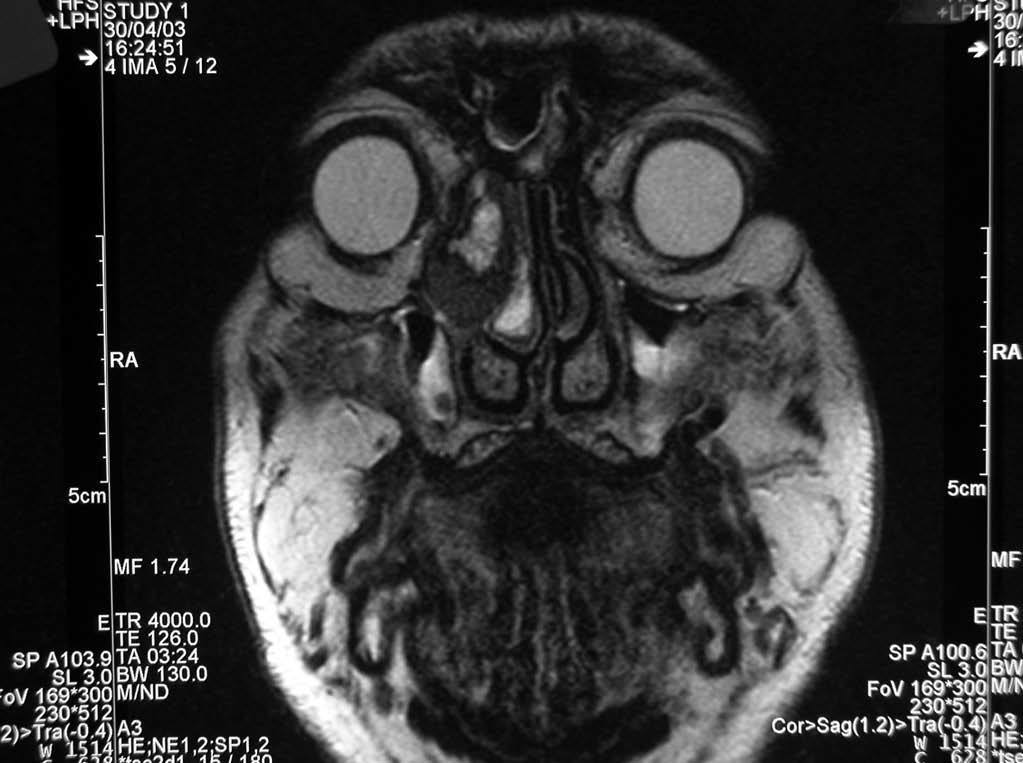

Se llevó a cabo una exéresis parcial de la lesión con fines diagnósticos y posteriormente se realizó una RM, que mostró (figs. 3 y 4) una mínima infiltración de la grasa orbitaria adyacente a la tumoración y descartó la afectación de la musculatura extrínseca ocular.

Fig. 4.--Resonancia magnética realizada tras la resección parcial del tumor. Corresponde a un plano coronal, potenciado en T2, en el que se pone de manifiesto la infiltración de la grasa orbitaria. Como hallazgo casual se observa una concha bullosa que se encuentra ocupada.